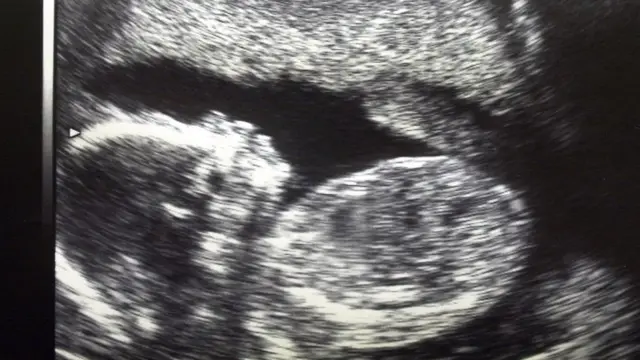

Hata hivyo Ovari zake hazikuwa na matatizo.Na madaktari walikuwa tayari kuondoa mayai, kuyarutubisha kwa kutumia mbegu za kiume za mumewe kisha kuzigandisha.

Katika kipindi cha wiki sita baadae, alianza kupata hedhi.

baada ya miezi saba, mayai yake yaliyorutubishwa yakapandikizwa.

Na baada ya mimba, mtoto wa kilo 2.5 alizaliwa kwa upasuaji tarehe 15 mwezi Desemba mwaka 2017.